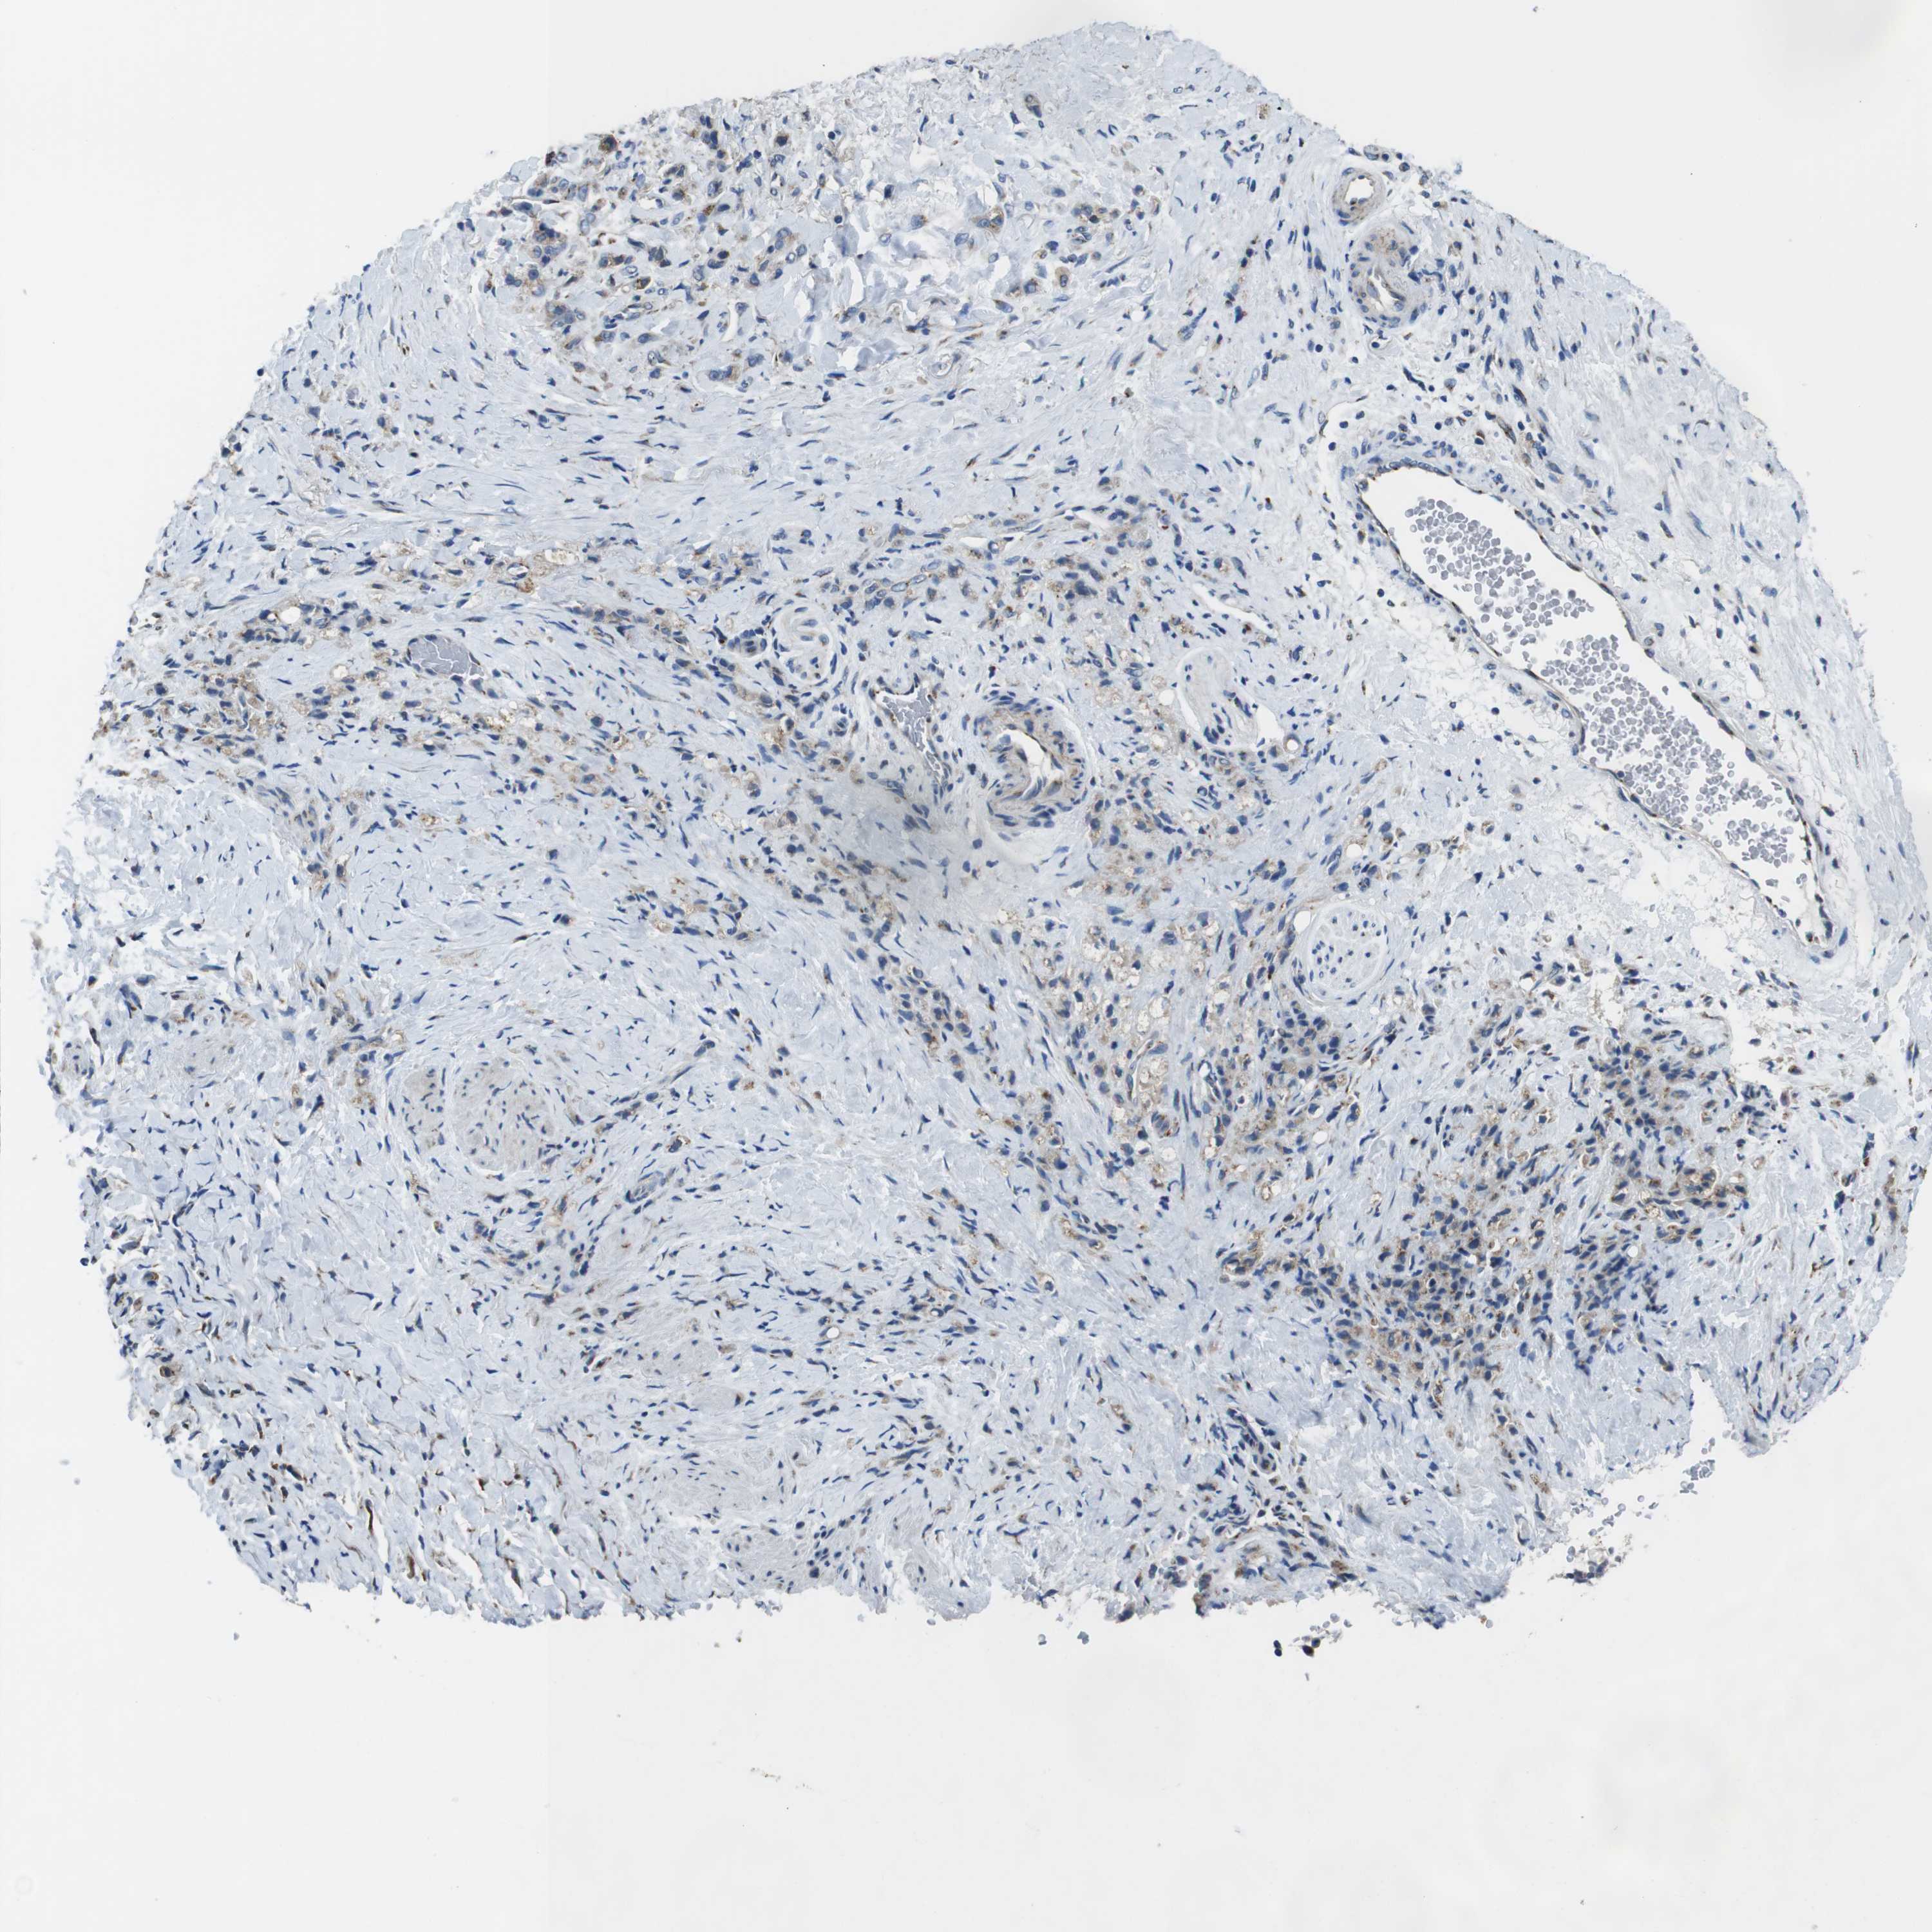

STOMACH CANCER - Protein expressioni

A mouse-over function shows sample information and annotation data. Click on an image to view it in a full screen mode. Samples can be filtered based on level of antibody staining by selecting one or several of the following categories: high, medium, low and not detected. The assay and annotation is described here.

Note that samples used for immunohistochemistry by the Human Protein Atlas do not correspond to samples in the TCGA dataset.

Antibody stainingi

Antibody staining in the annotated cell types in the current human tissue is reported as not detected, low, medium, or high, based on conventional immunohistochemistry profiling in selected tissues. This score is based on the combination of the staining intensity and fraction of stained cells.

Each image is clickable and will lead to virtual microscopy that enables deeper exploration of all samples and also displays staining intensity scores, fraction scores and subcellular localization as well as patient and tissue information for each sample.

Antibody HPA059131

Antibody CAB009936

Staining

High

Medium

Low

Not detected

Intensity

Strong

Moderate

Weak

Negative

Quantity

>75%

75%-25%

<25%

None

Location

Nuclear

Cytoplasmic/membranous

Cytoplasmic/membranous,nuclear

Adenocarcinoma, NOS

Adenocarcinoma, High grade